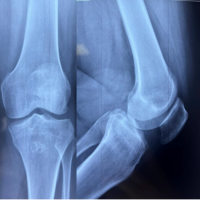

A 48-year-old male presented to the emergency department following a motor vehicle accident with complaints of severe pain, swelling, and inability to bear weight on his left lower limb. On examination, there was significant swelling around the knee joint with marked tenderness over the medial femoral condyle. The patient was unable to perform active knee flexion or extension. Distal neurovascularity was intact. Initial radiographs revealed a coronal plane fracture of the medial femoral condyle, consistent with a Hoffa fracture. In addition, a displaced PCL avulsion fracture was seen (Fig. 1).

Figure 1: Pre-operative X-rays showing a medial Hoffa fracture with the posterior cruciate ligament avulsion fracture.